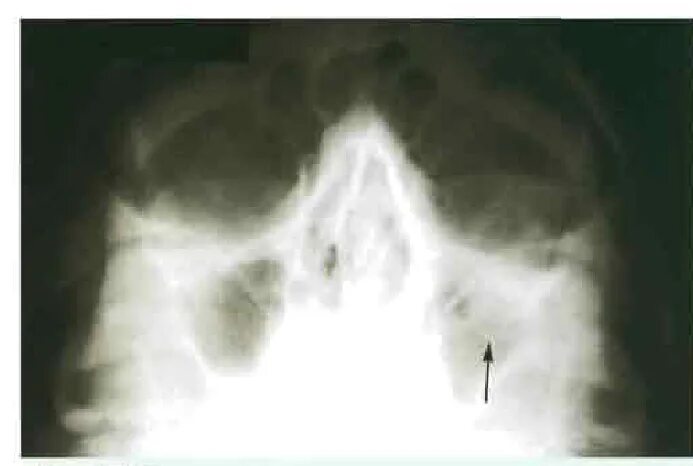

Перелом стенки левой орбиты